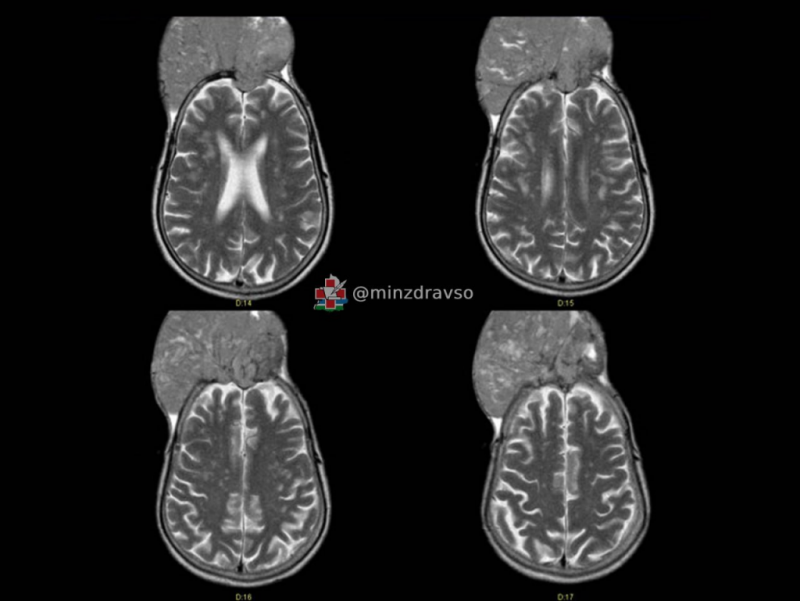

Хирурги из Свердловского областного онкологического диспансера спасли жителя краснотурьинца, у которого опухоль мозга буквально проросла через череп.

Как рассказали на информационном ресурсе «Здоровье уральцев» министерства здравоохранения региона, у мужчины была менингиома – одна из самых распространённых опухолей. Она доброкачественная, но может вызывать нарушения слуха, зрения, речи, чувствительности, двигательной активности, и без своевременной терапии создавать угрозу для жизни.

Этот пациент поступил в отделение нейроонкологии, когда опухоль «съела» кости черепа и выросла наружу на 10 сантиметров.

«При этом она не вызвала никаких симптомов. На вопрос, почему так долго не обращался к врачам, хотя "вторая голова" росла буквально на глазах, мужчина ответить затруднился. В итоге новообразование достигло размеров примерно 15 на 15 сантиметров»,

– рассказал нейрохирург Свердловского областного онкодиспансера Павел Гвоздев.